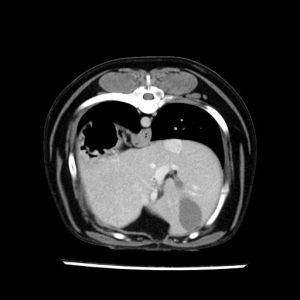

La lesione focale epatica , la ceus,la Tac e il chirurgo .